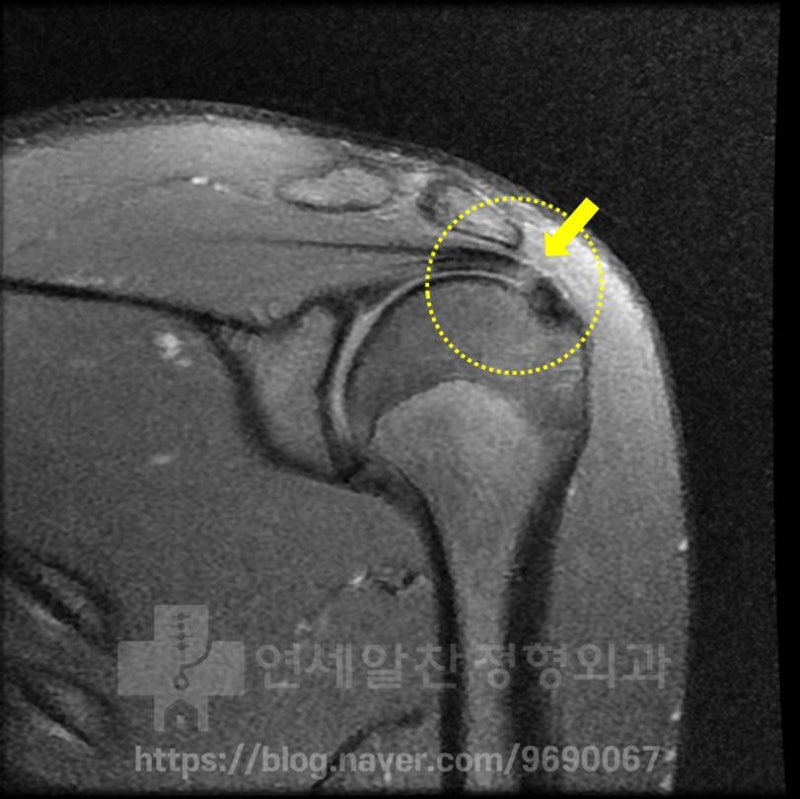

X-ray 사진에서 보았을때 전혀 문제 없는 정상적인 소견이 관찰되었습니다.

MRI 를 살펴보았을 때 노란 점선안에 보이는 극상근 부위에서 화살표 부위로 표시된 곳이 약간 하얗게 보이는 소견이 관찰됩니다. 이는 극상근내 염증소견이 있는 것을 나타내며 이것을 부분 파열이라고 진단하고 재생주사치료를 한 것으로 보입니다. 하지만 이 MRI 소견으로는 단순 염증 정도로 보이며 파열까지는 진행되지 않은 것으로 보입니다. 시간이 어느정도 경과 되었기 때문에 초음파를 통해 다시 한번 검사를 해 보기로 하였습니다.